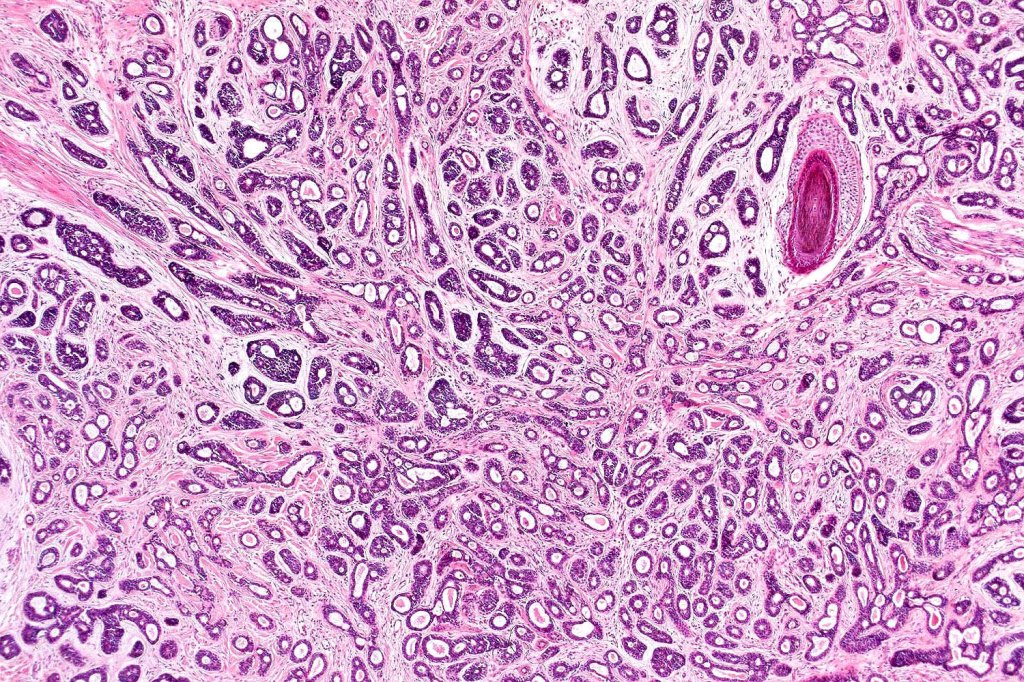

Histological features

•Biphasic tumor (myoepithelial & epithelial)

•Cribriform nests, tubules , cords & solid nodules

•Presence of myoepithelial cells

•Small ducts and pseudocysts

•Perineural infiltration*